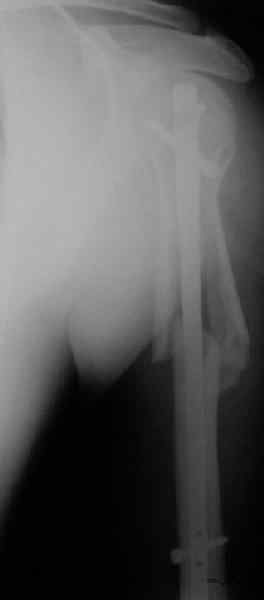

Попытка закрыто изменить положение не удалась. Передним доступом сделали открытую репозицию, гленоид без особенностей. Временно фиксировали спицами и остроконечным костедержателем. Фиксировали гвоздем T2 PHN (Stryker). Для профилактики вывихов после введения проксимальных винтов ротировали дистальный отдел кнаружи на 30

градусов как аналог остеотомии по Weber. Снимки в приложении. Комментарии и критика привествуются.

Attempt of closed reduction failed. Open reduction via anterior approach. The head was temporarily fixed by wires and sharp clamps. Fixation by a nail - T2 PHN (Stryker). The distal fragment has been rotated 30 degrees externally after proximal locking for dislocation prevention as "virtual" Weber osteotomy. Images attached.

Comments/critics are welcome.